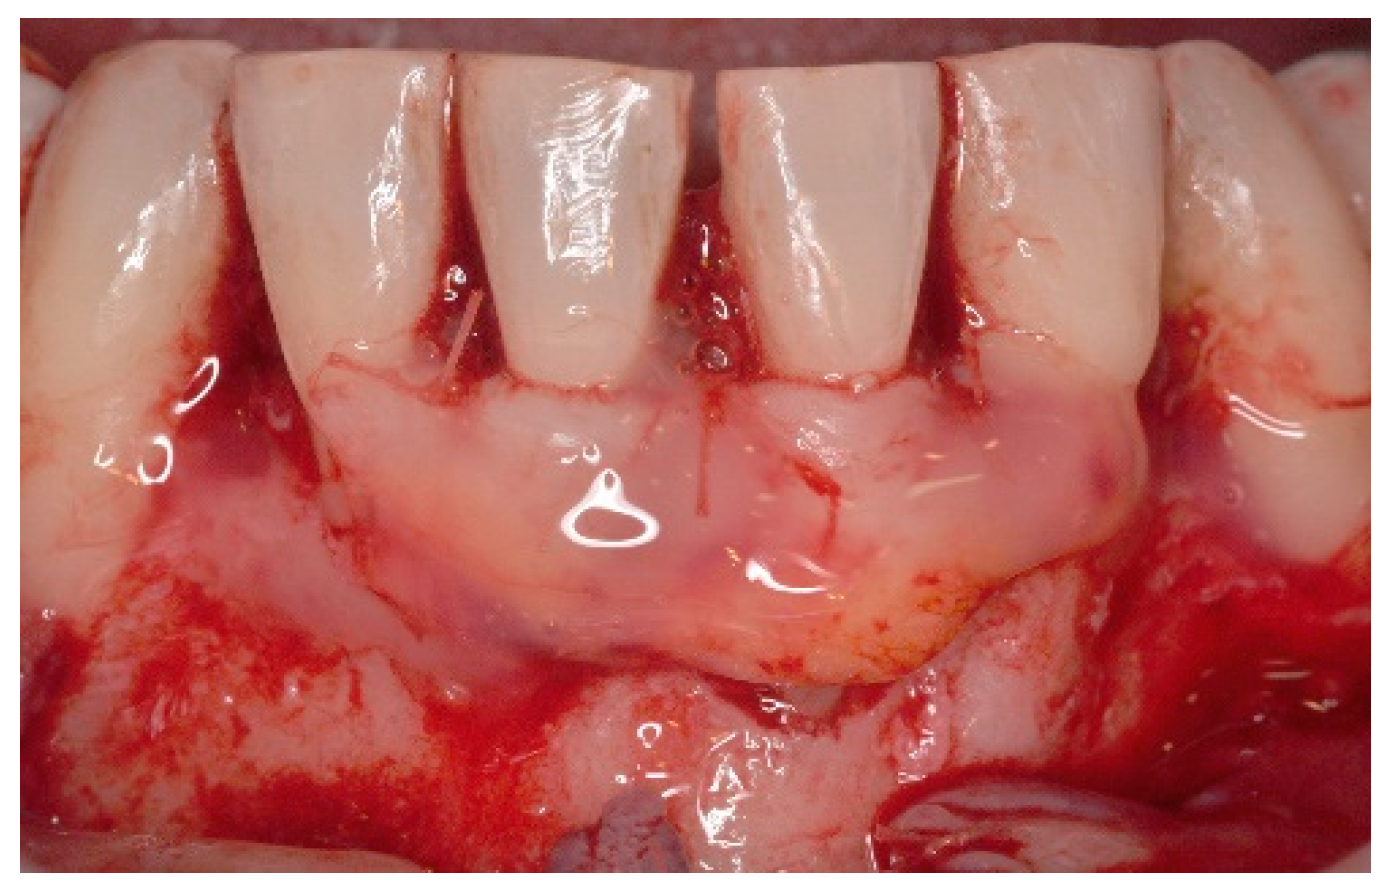

4. Free Connective Tissue Grafts in Periodontal Regenerative Procedures

5. Materials and Methods